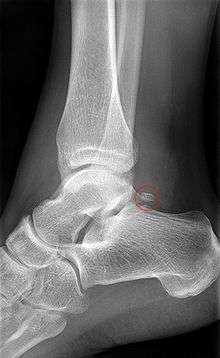

Os trigonum on x-ray.

The body features several prominent articulate surfaces: On its superior side is the trochlea tali, which is semi-cylindrical,[4] and it is flanked by the articulate facets for the two malleoli.[2] The ankle mortise, the fork-like structure of the malleoli, holds these three articulate surfaces in a steady grip, which guarantees the stability of the ankle joint. However, because the trochlea is wider in front than at the back (approximately 5–6 mm) the stability in the joint vary with the position of the foot: with the foot dorsiflexed (toes pulled upward) the ligaments of the joint are kept stretched, which guarantees the stability of the joint; but with the foot plantarflexed (as when standing on the toes) the narrower width of the trochlea causes the stability to decrease.[5] Behind the trochlea is a posterior process with a medial and a lateral tubercle separated by a groove for the tendon of the flexor hallucis longus. , the lateral of these tubercles forms an independent bone called os trigonum or "accessory talus"; it may represent the tarsale proximale intermedium. On the bone's inferior side, three articular surfaces serve for the articulation with the calcaneus, and several variously developed articular surfaces exist for the articulation with ligaments.[2]